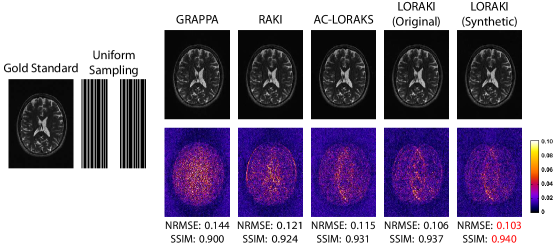

Figureย 2, Tableย 1, and supporting Fig.ย S1 show results from reconstructing uniformly-undersampled T2-weighted data. In this specific case, we simulated an acquisition that measured every fourth line of k-space, while also fully-acquiring the central 32 phase encoding lines to be used as ACS data. Taken together, this results in an effective acceleration factor of . As can be observed from Fig.ย 2 and Tableย 1, the proposed LORAKI approach had the best performance in all cases, with uniformly lower NRMSE values and uniformly higher SSIM values compared to GRAPPA, RAKI, or AC-LORAKS. We observed similar NRMSE and SSIM values for LORAKI when using the original ACS data or when using synthetic ACS data generated from an initial AC-LORAKS reconstruction of the data. In this specific case, the amount of acquired ACS data is already relatively high, which may explain the relative lack of impact from using synthetic ACS data. A corresponding ESP plot shown in supporting Fig.ย S1 shows that LORAKI approaches have consistently similar or better error characteristics than other methods across all spatial frequencies, with the most significant advantage at high-spatial frequencies.